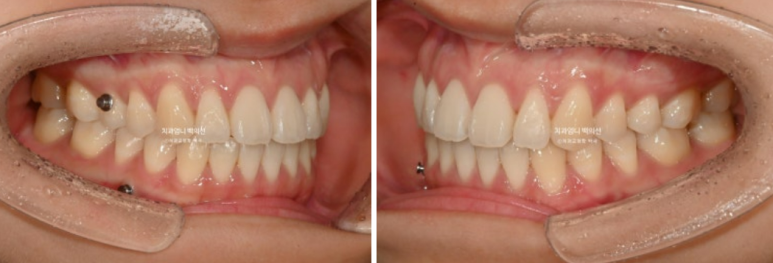

23년 11월 개방교합 치료를 위해 내원한 환자분입니다.

앞니 돌출감도 느끼는 상태입니다.

23년 12월 1번장치를 끼기 시작해서 25년 1월까지 총 51개 장치를 다 낀 후 모습입니다.

25.01

앞니 개방교합은 해소가 되었지만 앞니 중심선 불일치가 약 1mm 남았습니다.

우측 어금니 교합은 약간 떠있는 상태이고

좌측 어금니 교합은 좋습니다.

배열도 좋습니다.